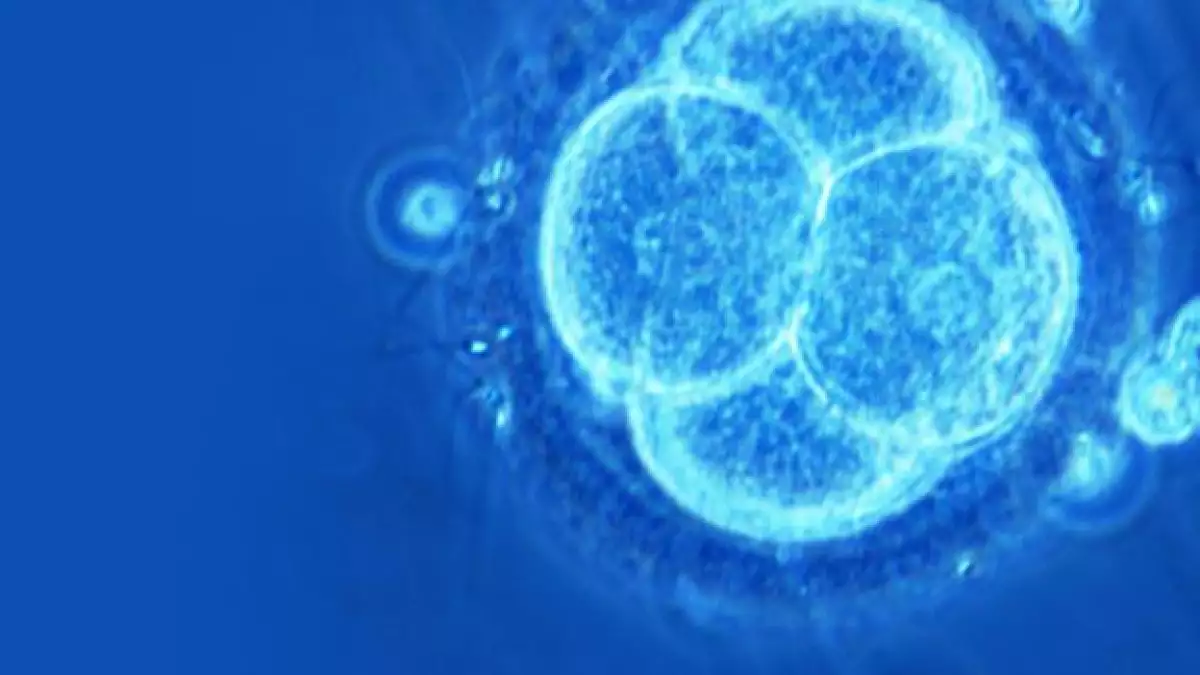

Lo que los científicos de Oregon han hecho es dar luz a lo que los aspirantes a clones humanos han esperado durante 15 años, lo que parece ser una técnica fiable para la creación de embriones clonados. Creo que fue irresponsable publicar sus investigaciones antes de que haya una prohibición integral mundial de la clonación, con duras sanciones.

El elemento de la clonación existe meramente para fines de crear tejidos genéticamente idénticos para el paciente, que no serán rechazados,y esa es una buena idea. El problema es que ello trae toda una serie de problemas biológicos que crean mayores riesgos para el paciente, así como la creación de un proceso muy, pero muy caro.

Con la clonación, se está forzando a la naturaleza a hacer algo que ella no quiere, por lo que son de esperarse nuevos riesgos. La clonación crea anomalías en la lectura de salida genética, lo cual es la causa por la que los animales clonados se enferman con frecuencia. Dichos errores estarán allí, en cualquier célula madre y en los tejidos producidos a través de la clonación. Esos problemas son otra de las razones por la cuales clonar bebés sería algo muy poco ético, pero no necesariamente hacen que sea imposible.